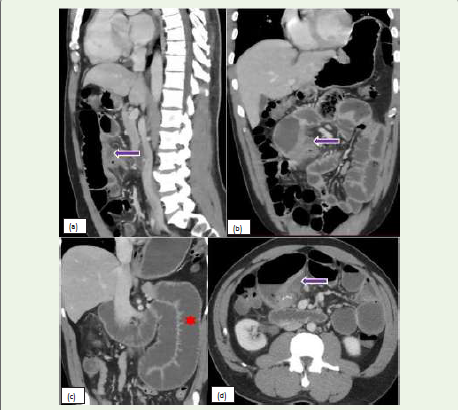

Figure 8: (a, b, c, d):Sagittal, coronal, and Axial CT images of a 42-year-old

male with a past story of gunshot injury to the abdomen, post exploratory

laparotomy presenting with acute upper abdominal pain, distension, nausea,

vomiting, and diarrhea. CT scan of the abdomen and pelvis with IV contrast

shows high-grade bowel obstruction (red star) with the transition to the level

of jejunojejunal anastomosis in the mid abdomen. There is a small Fluid

collection adjacent to the anastomotic site (purple arrow), suggestive of

anastomotic leak. In addition, adjacent bowel wall thickening suggestive of

inflammation is noted.